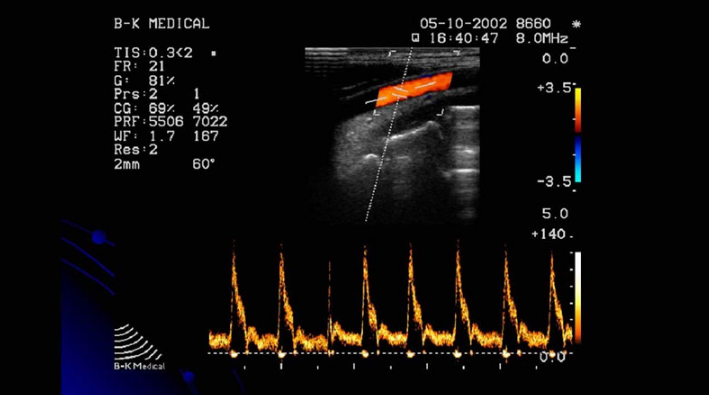

Có 4 kiểu siêu âm Doppler: Siêu âm doppler liên tục, siêu âm Doppler năng lượng, siêu âm Doppler xung và siêu âm Doppler màu. Siêu âm Doppler màu là một kỹ thuật chẩn đoán hình ảnh dựa vào nguyên lý của hiệu ứng Doppler nhằm khảo sát bất cứ dòng chảy nào bên trong cơ thể người. Khi một chùm tia siêu âm được phát đi gặp một vật sẽ phản hồi âm, nếu khoảng cách tương đối giữa nguồn phát và vật thay đổi, tần số của chùm siêu âm phản hồi sẽ thay đổi so với tần số của chùm siêu âm phát đi.

Trong quá trình siêu âm Doppler, bác sĩ đặt đầu dò lên da của người được siêu âm và di chuyển trên vị trí cần kiểm tra. Các sóng âm từ đầu dò phát ra dội lại các vật thể chuyển động và phản xạ tạo ra hình ảnh bên trong cơ thể người. Máy siêu âm sẽ tổng hợp và hiển thị hình ảnh trên màn hình dưới dạng các dạng sóng phổ khác nhau, các màu sắc hoặc tín hiệu âm thanh có thể nghe được.